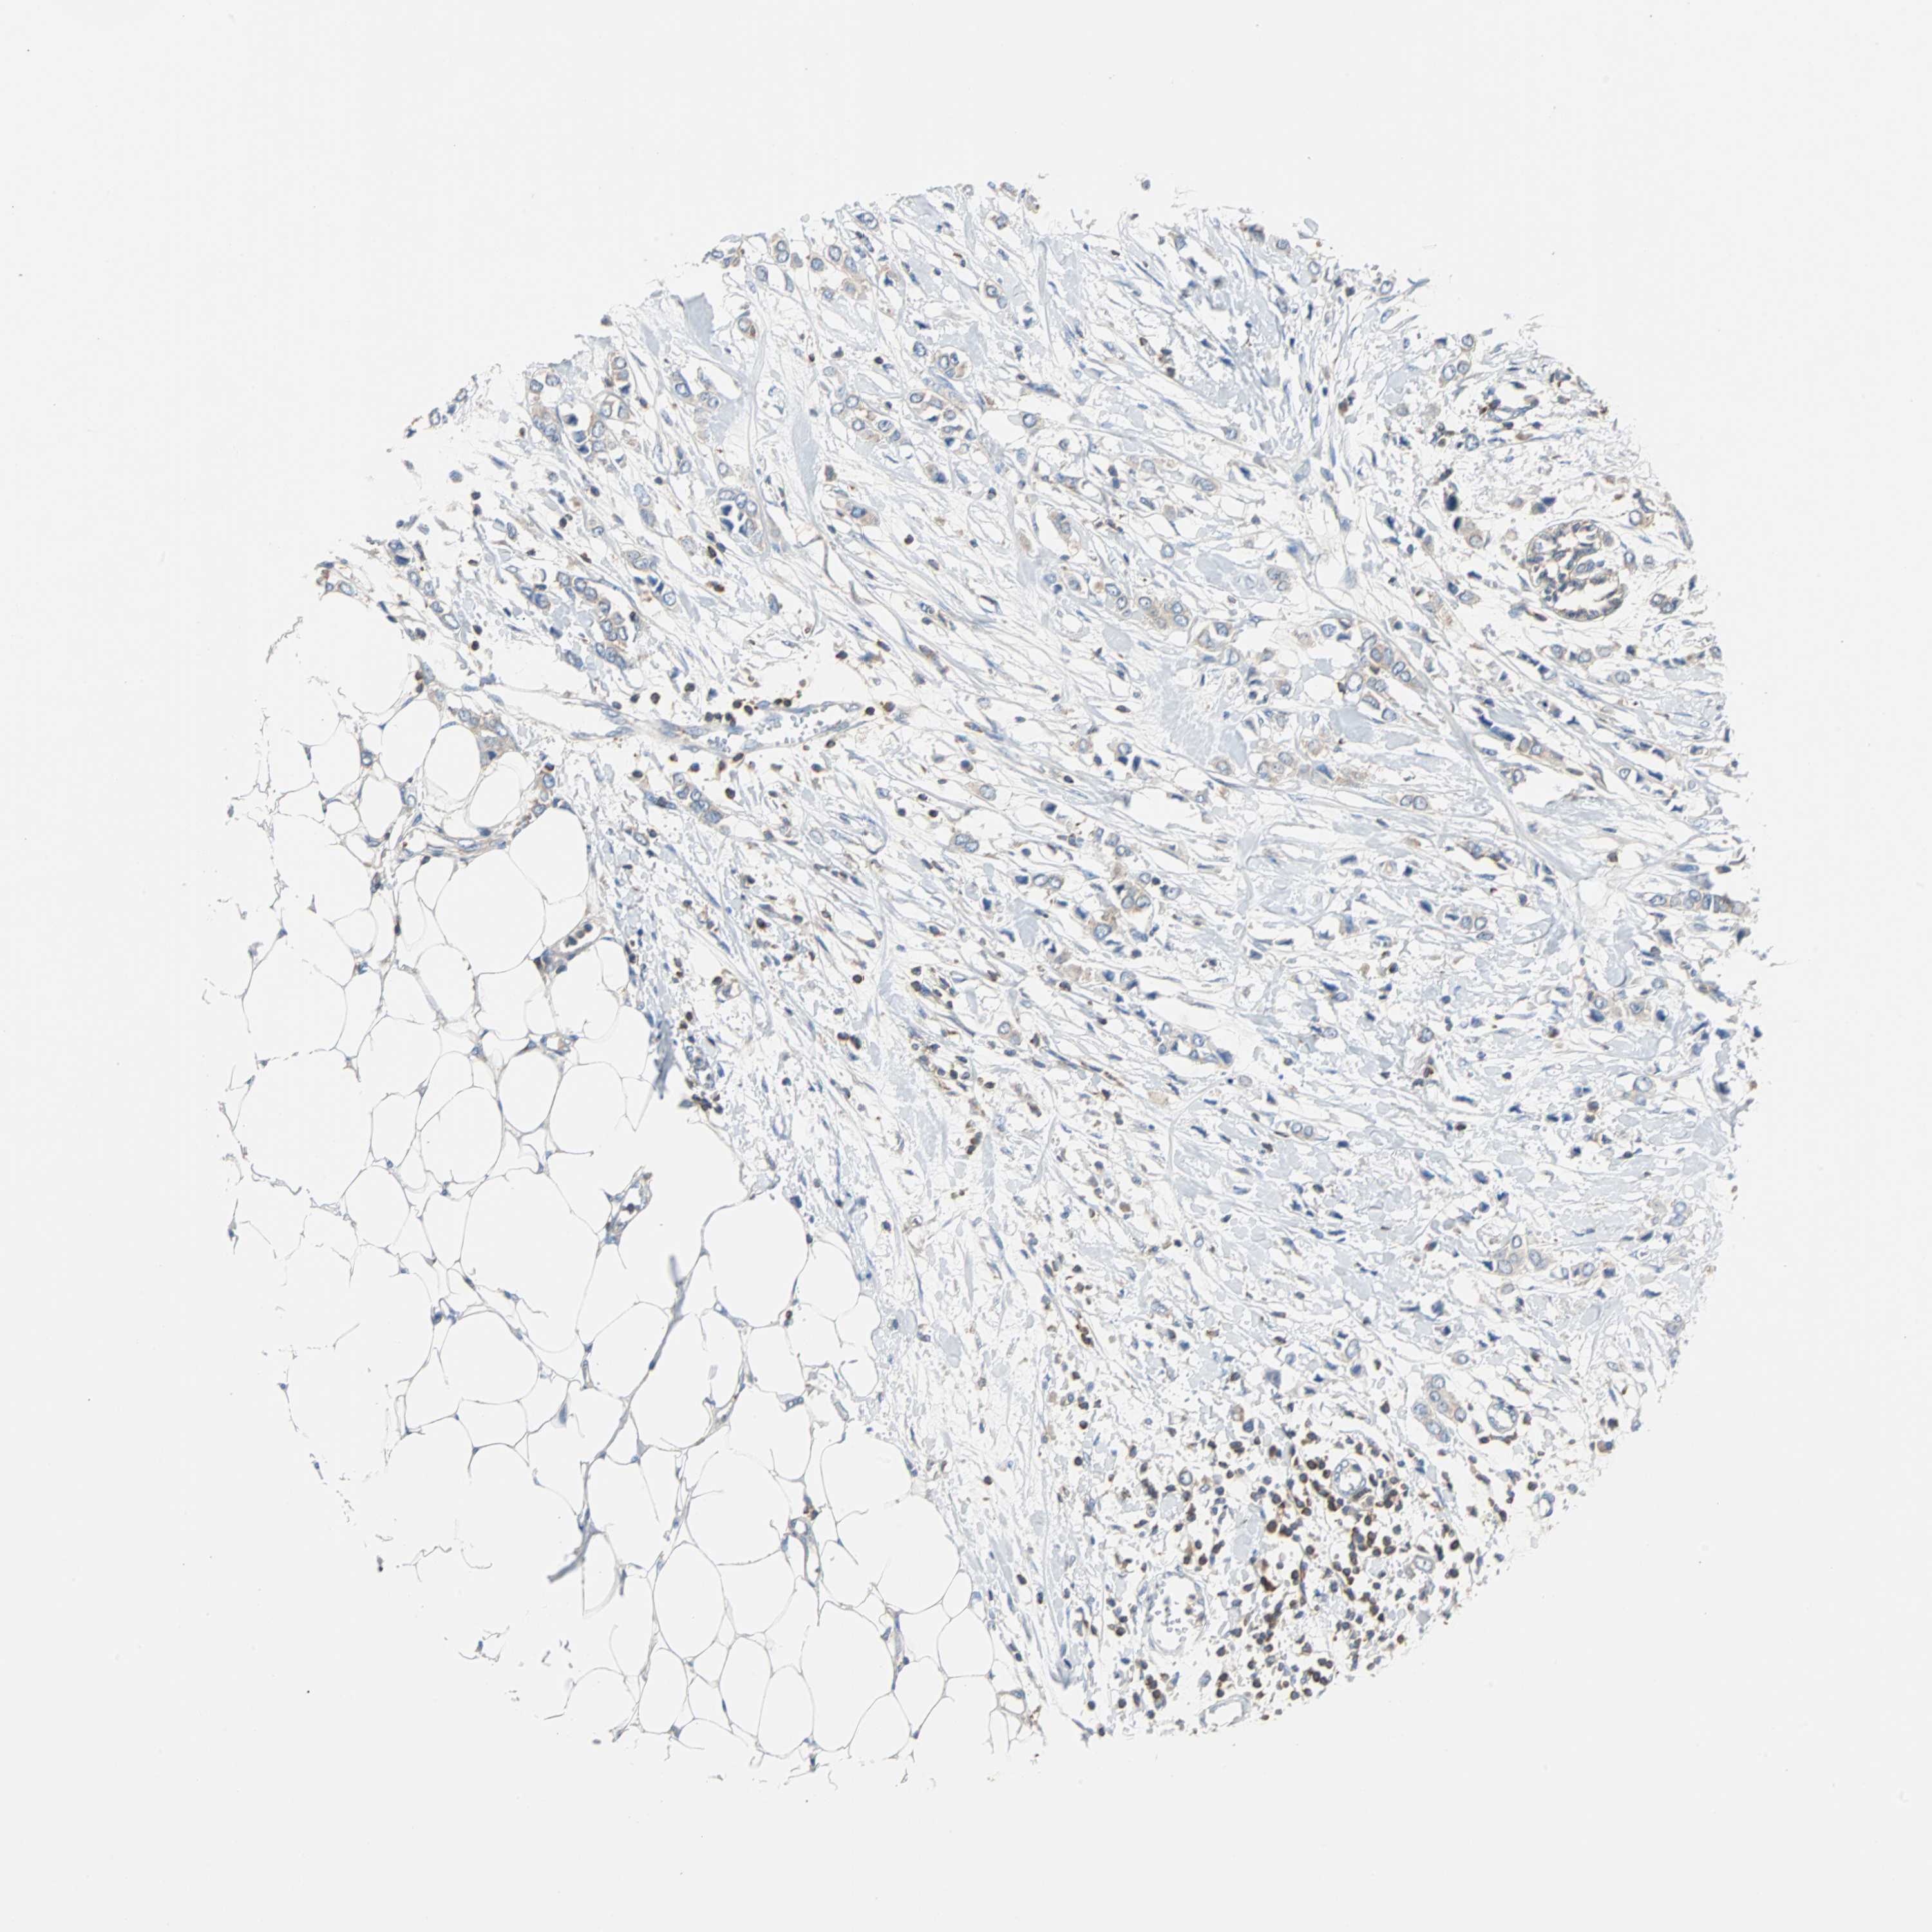

BRCA TCGA BRCA VALIDATION PROTEIN EXPRESSION